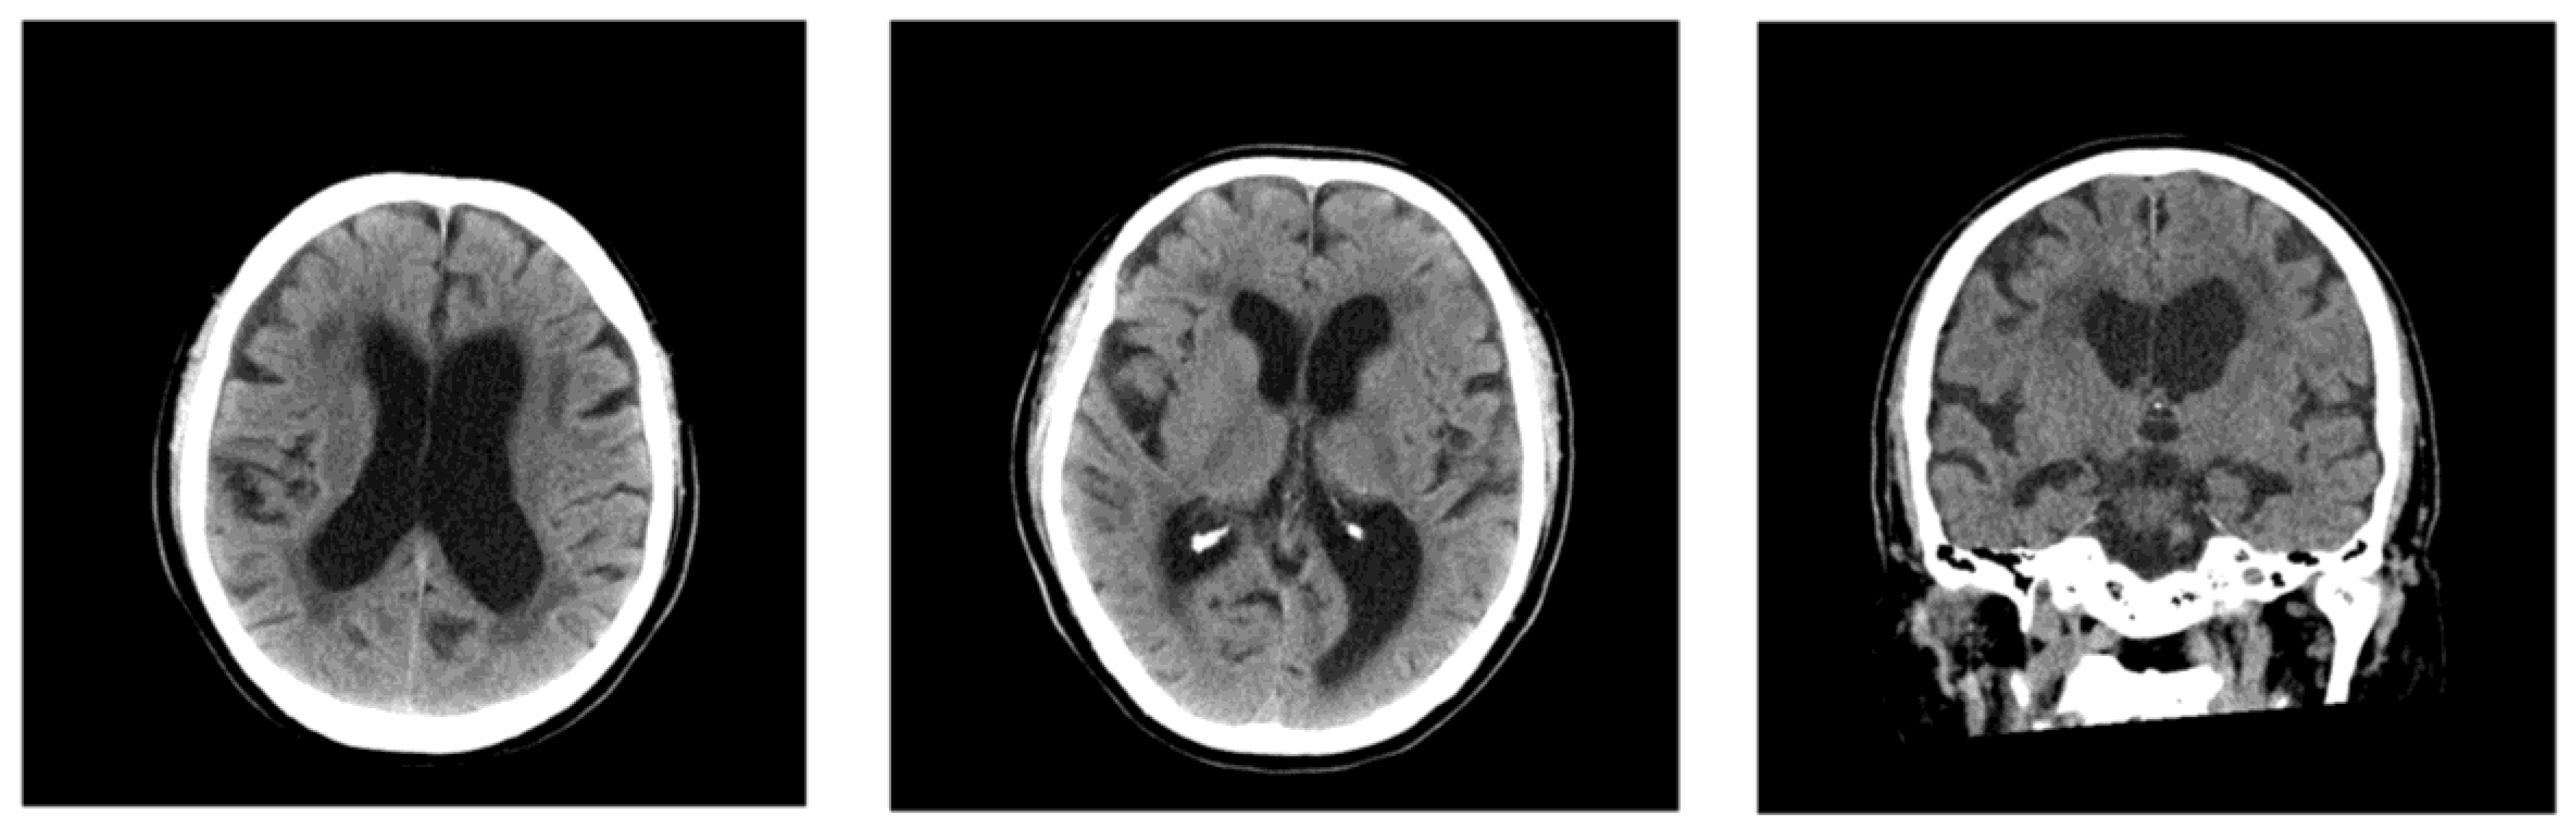

Initial head CT demonstrated bilateral periventricular hypodensities, and the patient’s Evans index [11] was 0.34 (Figure 1). Mild enlargement of the Sylvian fissures was noted and the subarachnoid spaces over the high convexity appeared slightly narrowed, suggesting the absence of disproportionally enlarged subarachnoid space hydrocephalus (DESH) features. On hospital days 1 and 2, the four sets of blood cultures performed tested positive for Gram-negative rods, and treatment with intravenous meropenem was initiated for sepsis. Because of the patient’s elevated D-dimer levels and clinical presentation, transient ischemic attack or cerebral venous thrombosis were considered; however, echocardiography and lower-extremity venous ultrasound revealed no evidence of thrombosis.

Figure 1. Head CT on admission in Case 1, showing bilateral periventricular hypodensities and ventricular enlargement. The patient’s Evans index was 0.34. His Sylvian fissures were mildly enlarged, and the subarachnoid spaces over the high convexity were slightly narrowed and did not exhibit typical DESH features.